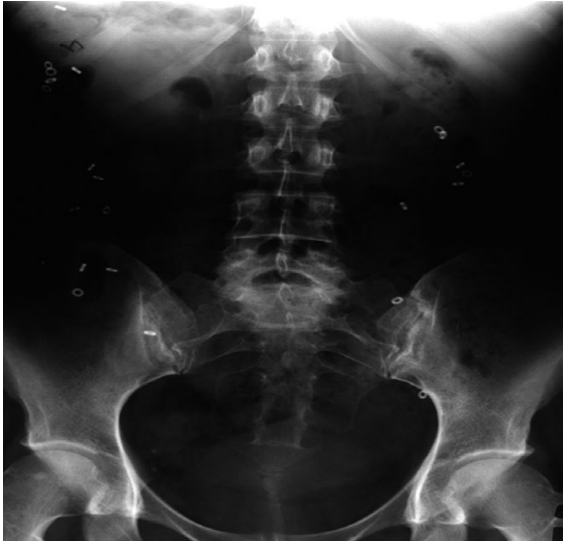

Trong số phương pháp trên, kỹ thuật đánh dấu cản quang với Sitzmarks đơn giản và được sử dụng phổ biến nhất. Không cần thiết làm sạch ruột trước khi thực hiện. Thử nghiệm này được thực hiện bằng cách uống một viên nang chứa 24 vòng cản quang, sau đó chụp X – quang bụng ở tư thế đứng vào ngày thứ 3 hoặc ngày thứ 5 kể từ khi uống viên nang. Lưu thông ĐT bình thường khi có >80% số vòng được đào thải. Lưu thông ĐT chậm khi có >20% (≥6 vòng) còn lại vào ngày thứ 3 hoặc ngày thứ 5.Một hình ảnh minh hoạ lưu thông ĐT chậm được chụp vào ngày thứ 5 sau khi uống 24 vòng cản quang, có 21 vòng bị giữ lại trong ĐT.

![]() |

| Hình 3. Đánh giá lưu thông đại tràng bằng Sitzmarks “Nguồn: Bharucha, 2019" |